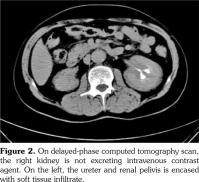

A 51-year-old male patient admitted to our outpatient clinic with complaints of flank pain and fatigue. He had a history of renal stones and peripheral arterial disease. He had a medically unmanageable hypertension. Blood pressure was 200/110 mmHg. Serum creatinine level was 1.2 mg/dL. He was evaluated with contrast- enhanced multislice computed tomography. Along with small calyceal stones, there was bilateral, quite symmetrical perinephric ''rind-like'' soft tissue infiltration. Right kidney was atrophic but still functioning without pelvicalyceal contrast excretion. The soft tissue infiltration obliterated both renal hila and caused proximal ureteral stenoses with mild calyceal dilation on the left side (Figures 1 and 2). Distally, the ureters were normal. Incidentally, abdominal aorta, common iliac arteries, proximal celiac trunk, and proximal renal arteries were noticed to appear “coated” with subtle perivascular tissue infiltration. An endovascular aortoiliac stent-graft was in place. He rejected any further diagnostic intervention after he presented with a blood creatinine of 2.2 mg/dL. He underwent an unenhanced computed tomography examination with the same findings before. Renal scintigraphy revealed a non-functioning right kidney. Perinephric soft tissue infiltration was considered as the differential diagnosis of ECD. Direct radiographies of the extremities were obtained. All of the long tubular bones showed diametaphyseal cortical and patchy medullary sclerosis reinforcing the diagnosis of ECD (Figure 3). The patient underwent right nephrectomy for the control of hypertension and a double-J stent was placed on the left side for the relief of ureteral obstruction. The nephrectomy specimen showed the typical histological features of ECD. Serum creatinine level dropped to the borderline values after the operation and his blood pressure was in the normal range with medications. The pathological analysis of the nephrectomy specimen revealed an inflammatory infiltrate formed by foamy histiocytes that were positively stained for CD68 and neutrophilic aggregates which confirmed the preoperative diagnosis (Figures 4 and 5). A written informed consent was obtained from the patient.

The histiocytic infiltrative process, as found in our case, may involve the retroperitoneum in approximately 29 to 68% of patients.(4,5) The soft tissue infiltrate around the aorta and its major branches can be misdiagnosed as arteritis, lymphoma or retroperitoneal fibrosis.(4) The process may lead to severe arterial stenosis and the consequences include cerebral ischemia, cardiac angina, mesenteric ischemia, or renovascular hypertension.(6-8) Adrenal glands, kidneys, renal arteries, ureters, and adjacent anatomical spaces may be involved in the process. Infiltration of perirenal space may extend to the pararenal space with irregular borders, thus will be given the name “hairy kidney”.(6) Extension to the renal sinuses and pedicles, proximal and distal ureters is possible and may cause obstruction and eventually, as in our case, compromise renal function.(8-10)